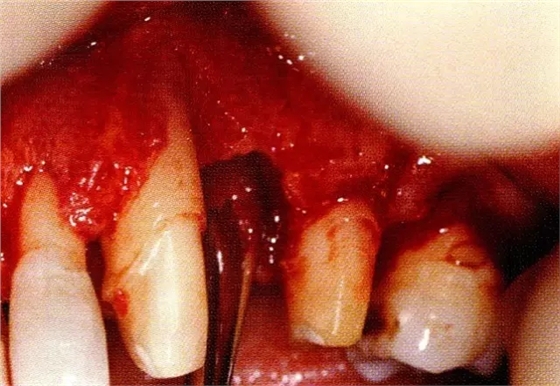

案例3針對(duì)3壁性垂直性骨缺損使用非吸收性膜進(jìn)行再生治療,再翻瓣時(shí)進(jìn)行骨形態(tài)修整的病例。

▲圖7-1左下6近中可觀察到3壁性垂直性骨缺損。此病例考慮到齦瓣供血關(guān)系,在前磨牙部位進(jìn)行了減張切開,沒有進(jìn)行縱切開。并利用刮治器、牙周外科用車針進(jìn)行了徹底的骨缺損部位搔刮。